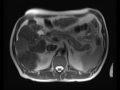

Hepatocellular Carcinoma (Hepatoma) (HCC)

Multiple MR images demonstrate a T2 bright, hypervascular mass in the right hepatic lobe with evidence of delayed washout, compatible with hepatocellular carcinoma